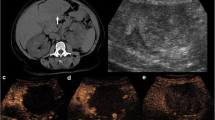

MRI is the modality of choice for evaluating CRLM and has proven to be highly effective for hepatic parenchymal assessment. Compared to CT, MR images offer superb soft tissue contrast, which improves diagnoses of intrahepatic lesions due to greater liver-to-lesion contrast difference (Fig. 5.2) [17]. MRI also excels in detecting small lesions (<10 mm) and identifying CRLM in patients undergoing NAC or have hepatic steatosis (Tables 5.2 and 5.3) [19, 23, 31]. Dynamic contrast-enhanced MRI (CE-MRI) with hepatobiliary agents and diffusion-weighted imaging (DWI) has further improved CRLM detection and characterization of indeterminate lesions, especially for small lesions [32,33,34,35]. Gadoxetate disodium (Gd-EOB-DTPA, Eovist in the USA) is the most commonly used hepatobiliary agent with MRI for CRLM detection with a pooled sensitivity of 93.1% (Table 5.3) [19].

Value of MRI for detection of metastasis in background of fatty liver. A 58-year-old male with CRLM and diffuse hepatic steatosis. Post-contrast T1-weighted axial MR images (a, b) reveal peripherally enhancing hypointense lesions (arrows) that are not discernible on post-contrast axial CT (c, d) images due to uniformly low attenuation of background liver parenchyma suggesting diffuse hepatic steatosis

MRI sequences for CRLM assessment usually include a combination of T1-weighted (T1W), T2-weighted (T2W), and diffusion-weighted images (DWI) [36]. CRLM typically appear hypointense in precontrast T1W images and hyperintense in T2W images [36]. On dynamic CE-MRI, CRLM appear mostly hypointense, similar to CECT [36]. Eovist allows for further assessment of intrahepatic lesions with hepatobiliary (HB) phase (20 minutes after contrast injection) [37]. On HB phase, normal hepatocytes appear hyperintense due to eovist uptake, whereas CRLM do not retain contrast remaining hypointense and appear more conspicuous [37]. On DWI, CRLM become hyperintense compared to the normal liver due to diffusion restriction [38]. However, some benign lesions may also appear hyperintense (T2 shine-through effect) on DWI and can be differentiated from CRLM by the use of apparent diffusion coefficients (the “ADC” map) [35] (Fig. 5.3).